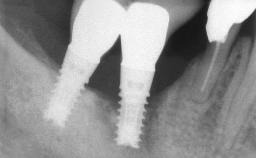

Excess Cement Resulting in Peri-implant Infection Presenting as a Draining Sinus Tract

Biological complications caused by undetected cement residue have been receiving much attention. Excess cement might be responsible not only for rapidly developing of peri-implantitis, but also for delayed or chronic manifestations of the disease many years after cementation (Wilson 2009; Linkevicius and coworkers 2013). Invitro and clinical studies have shown that it is very difficult or even impossible to completely clean up excess cement at subgingival margins, so popular in cemented restorations (Agar and coworkers 1997; Linkevicius and coworkers 2011, 2012). Possible outcomes of biological complications due to excess cement range from temporary inflammation of the peri-implant soft tissues without any serious esthetic and functional consequences all the way to implant loss. This report describes a case of peri-implantitis caused by residual cement; as well as the management and quite unusual resolution of the complication. The patient presented in 2009 with a draining sinus tract, tenderness on chewing, and tissue contact above the implant-supported restoration. The implant had been restored approximately three years before.